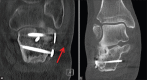

Figure 2

CT scan showing (a) Malreduction of a displaced, intraarticular calcaneal fracture despite open reduction and lateral plate fixation via an extensile approach. Such treatment combines the hazards and disadvantages of both operative and nonoperative treatment. Note the displacement of the peroneal tendons because of the displaced lateral fragment (red arrow). CT scan showing (b) A residual step-off in the subtalar joint which leads to significant load redistribution with the increased risk of posttraumatic arthritis. In the present case, there is complete loss of cartilage and cyst formation due to overload over the lateral aspect of the subtalar joint